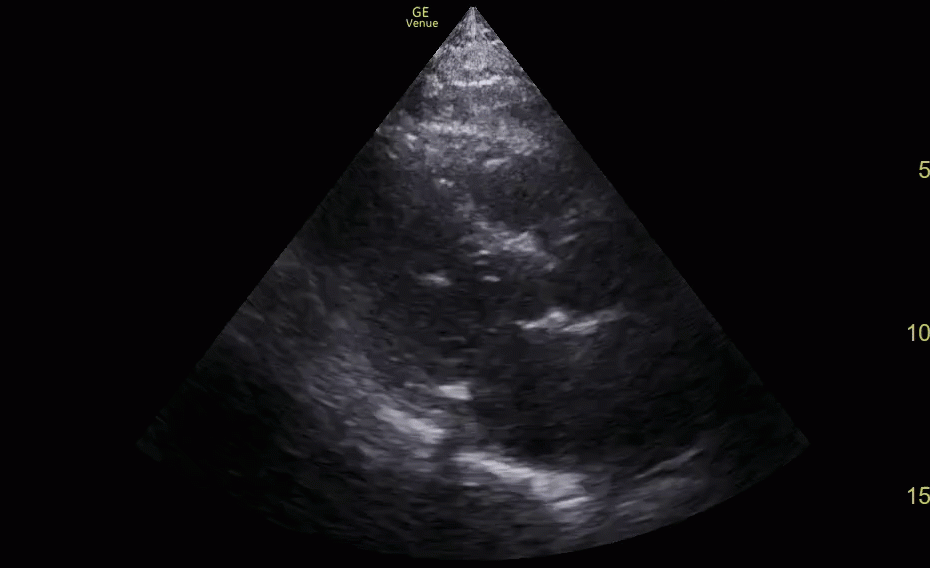

Pericardial and Pleural Effusions

Pericardial Effusion

Pacer Lead Migration

Mitral Valve Prolapse

Left Atrial Mass

Complete Heart Block

Atrial Flutter

Supine vs Left Lateral Decubitus

Normal 4 View Echo